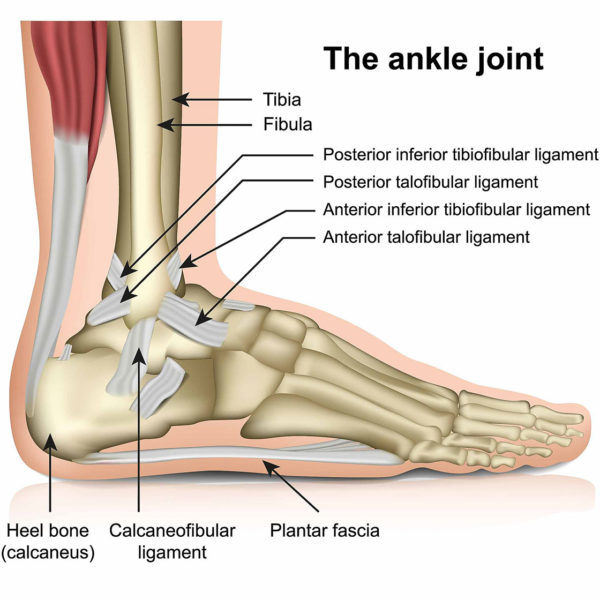

Achilles tendon injuries healthdirect 2025, Achilles Pain After Ankle Sprain Rehab 49 2025, Achilles Tendon Strain vs Sprain 2025, Strain vs Sprain What is the Difference 2025, Achilles Tendinitis Ankle Pain Foot Injury 2025, Achilles Pain After Ankle Sprain Rehab 49 2025, Achilles Tendon Pain Symptoms Causes Treatment Exercises 2025, Achilles Tendon Injuries Johns Hopkins Medicine 2025, Achilles Rupture Physiopedia 2025, Achilles Tendon Pain Causes Treatments Prevention 2025, Know the Symptoms of Achilles Tendonitis Tendinopathy Gait Happens 2025, Achilles tendon Overview Mayo Clinic Orthopedics Sports Medicine 2025, Achilles Pain While Running What It Means and What to Do 2025, Achilles tendon rupture Bupa UK Symptoms and treatment 2025, JCM Free Full Text Foundational Principles and Adaptation of 2025, Achilles Tendonitis Treatment Recovery Foot Pain Explored 2025, Anterior Talofibular Ligament Sprain 2025, Achilles Tendonitis Consultant Mr Andrew Roche FRCS London 2025, Micro tears of the Legs Strongest Tendon the Achilles 2025, Ankle Sprain NHS Lanarkshire 2025, Tendon Injuries of the Foot and Ankle Cal Sports Orthopaedic 2025, Sudden Ankle Pain Without an Injury Causes and Treatment 2025, Sprained Ankles Highgate Podiatry Biomechanics Orthotic Insoles 2025, Peroneal Tendinitis Symptoms Causes Diagnosis Treatments 2025, Sprained Ankle Treatment Rehabilitation Exercises 2025, Achilles Tendinopathy Causes Symptoms Treatment The Feet 2025, Sprained ankle Wikipedia 2025, Physiotherapy in Calgary for Achilles Tendon Problems 2025, Achilles tendon pain Achilles Tendonitis Move Osteopathy 2025, Ankle Sprain Foot Ankle Orthobullets 2025, Twisted Ankle sprain is it alright to walk with pain and 2025, Heel Pain Podiatrist in Old Bridge and Sayreville NJ Jason Grossman DPM 2025, Foot and Ankle Pain Keeping Me Well 2025, 4 Heel Pain Symptoms to Take Seriously Chicagoland Foot and Ankle 2025, Sudden Ankle Pain Without an Injury Causes and Treatment 2025, What Causes A Sore Achilles Tendon How Is It Treated by Usman 2025, Sprained Ankle vs. Rolled Ankle Advanced Ortho and Spine 2025, Achilles tendon pain Causes. when to see a doctor and treatment 2025, Best Ankle Braces for Sprains The Bracing Experts 2025, Tendinopathy Symptoms Causes Treatment 2025, Achilles Injuries Treatment Penn Medicine 2025, Ankle Sprains for Teens Nemours KidsHealth 2025, Achilles tendon pain Causes. when to see a doctor and treatment 2025, How to Heal a Ankle Injury using Sprain Ankle Treatment 2025, Hurt Your Ankle Use Our Ankle Pain Symptom Checker Tool 2025, How Do You Know if You Have Damaged Your Achilles Tendon 2025, Tips and Tricks Following a Sprained Ankle 2025, Common running ankle injuries everything you need to know 2025, Ankle Pain ankle ligaments sprain Everything You Need To Know Dr. Nabil Ebraheim 2025, Achilles Tendon Injury How Much Compensation Could I Claim 2025.

Twisted ankle achilles tendon pain 2025